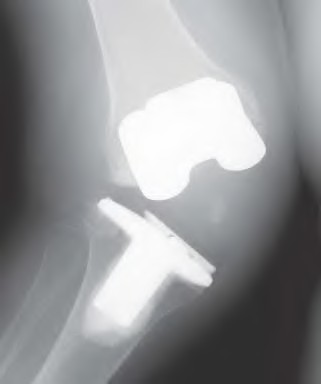

During a posterior-stabilized total knee arthroplasty, the surgeon assesses the gaps with trial components. The knee has a symmetric extension gap that accepts a 10 mm spacer block perfectly. In flexion, the gap is asymmetric, being tight medially and loose laterally. Which of the following is the most appropriate next step in management?

Explanation

During a revision total knee arthroplasty, removal of the tibial component reveals a massive contained metaphyseal defect measuring 3 cm deep, but with an intact cortical rim. According to the Anderson Orthopaedic Research Institute (AORI) classification, what type of defect is this, and what is the preferred method of management?

During a complex revision TKA, the surgeon notes profound laxity and attenuation of the medial collateral ligament (MCL) such that the knee cannot be balanced coronally in either flexion or extension. The extensor mechanism and posterior capsule remain completely intact. Which level of prosthetic constraint is most appropriate in this scenario?